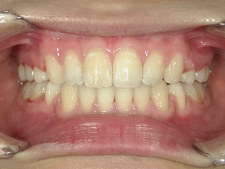

矯正歯科(全顎ワイヤー矯正)治療後

矯正歯科 治療後